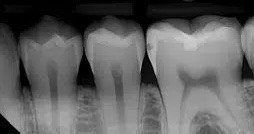

3. What surface require restoration?